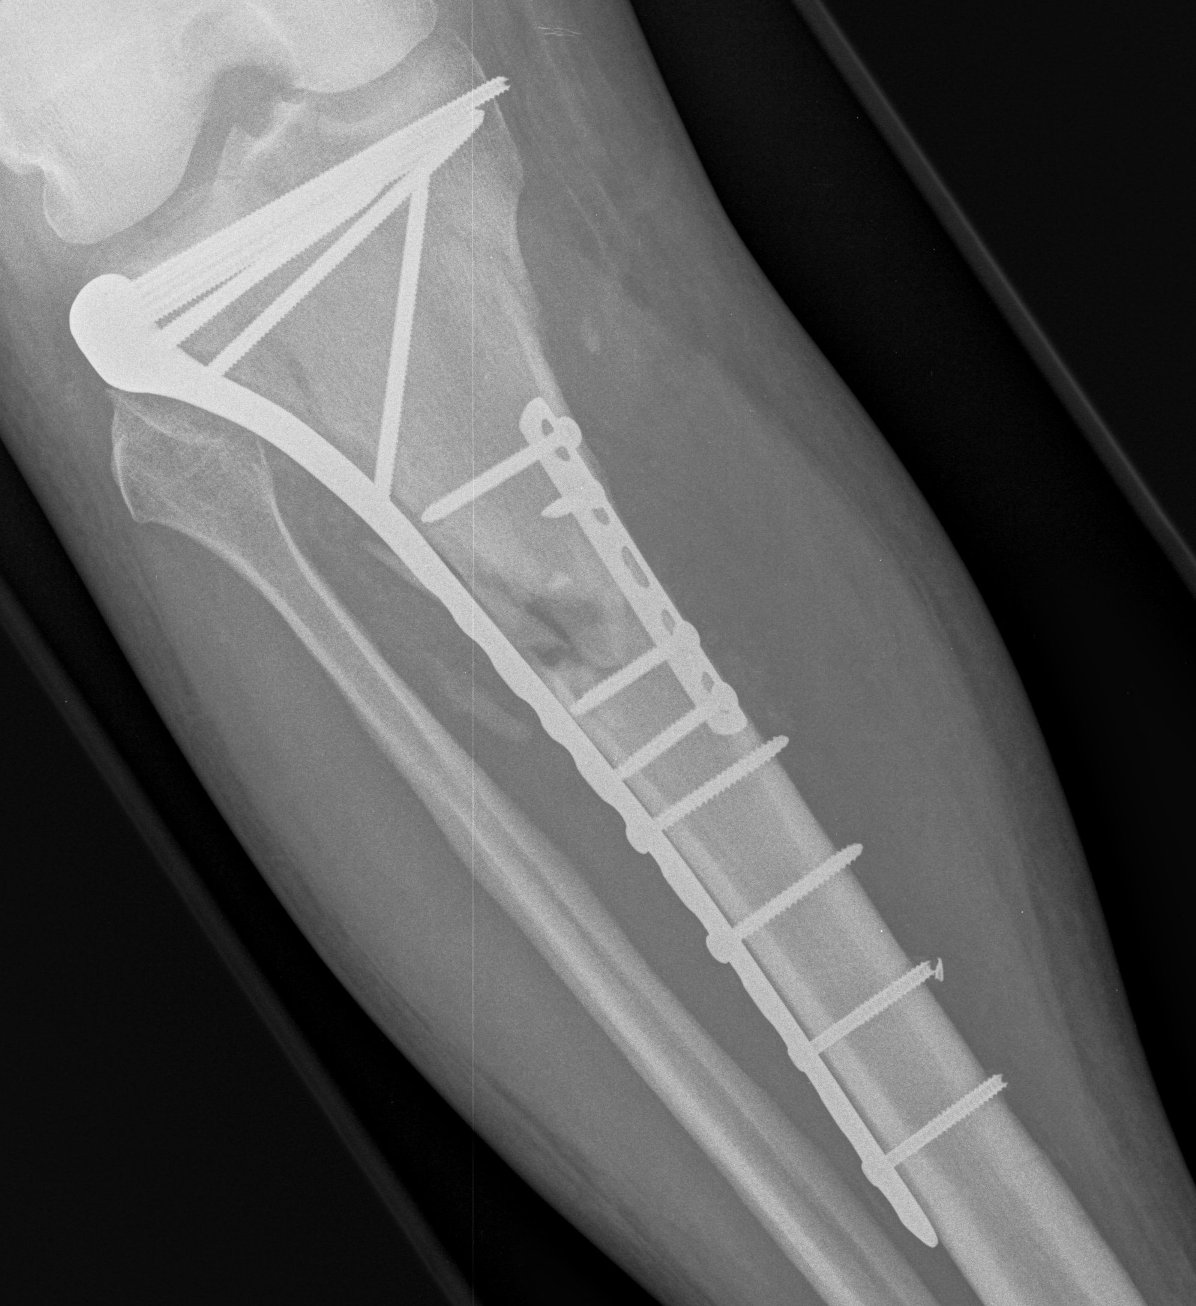

Type VI Bicondylar with Metaphyseal Fracture

Technique

- long locking plate minimally invasive with locking jig / MIPO

- proximal lag screws

- ensure correct alignment

- often use small medial buttress plate